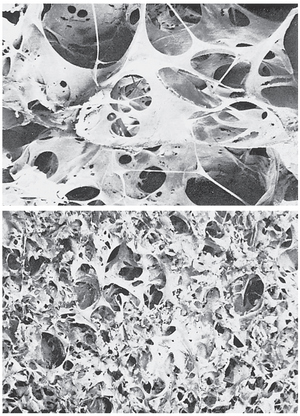

- 气道阻塞使得呼气特别困难,从而导致肺泡内空气滞留并过度扩张。这种效应与肺部感染相结合,导致多达50%至80%的肺泡壁显著破坏。因此,肺气肿的最终表现如图43-4(顶部)和43-5所示。

肺炎——肺泡中的炎症和液体

肺炎(pneumonia)一词包括任何肺部炎症状况,其中部分或全部肺泡充满液体和血细胞,如图43-5所示。一种常见的肺炎类型是细菌性肺炎(bacterial pneumonia),最常由肺炎球菌(pneumococci)引起。这种疾病始于肺泡感染;pulmonary membrane发炎并变得高度多孔,以至于液体甚至红细胞和白细胞从血液中渗入肺泡。因此,受感染的肺泡逐渐充满液体和细胞,感染通过细菌或病毒从肺泡到肺泡的扩展而传播。最终,肺部的大面积区域,有时是整个肺叶甚至整个肺,变得“实变(consolidated)”,这意味着它们充满了液体和细胞碎片。